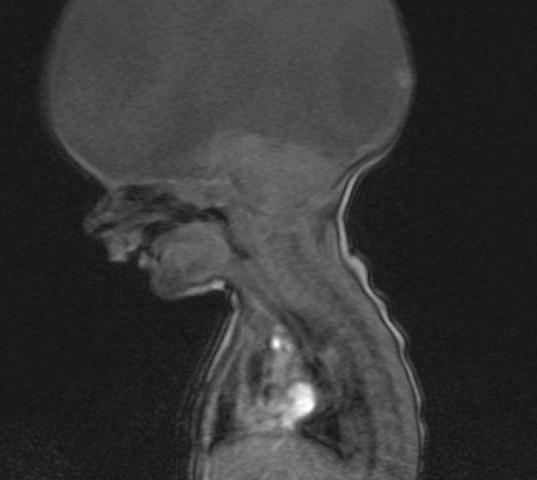

据报道 , 这位来自英国的妈妈24岁生下了自己的儿子 , 不幸的是 , 她的儿子患有全前脑畸形 , 也叫作前脑无裂畸形 , 这种病是因前脑发育障碍而引起的疾病 , 会导致孩子的颅面都畸形!!

通俗点说就是大脑不完整 , 只有脑干而已!从孩子刚出生的时候 , 医生一说孩子活不长 , 而且就这种情况 , 根本没有办法为孩子做移植大脑的手术!

得这种病的可能性只有八千分之一 , 而且神经和面部都会出现畸形!在孕检的时候 , 百分之八六的可以检查出来 , 但是这种病的神经系统出现畸形在产后是非常危险的 , 所以一定要认识检查即使终止其发育 , 这是最好的办法!